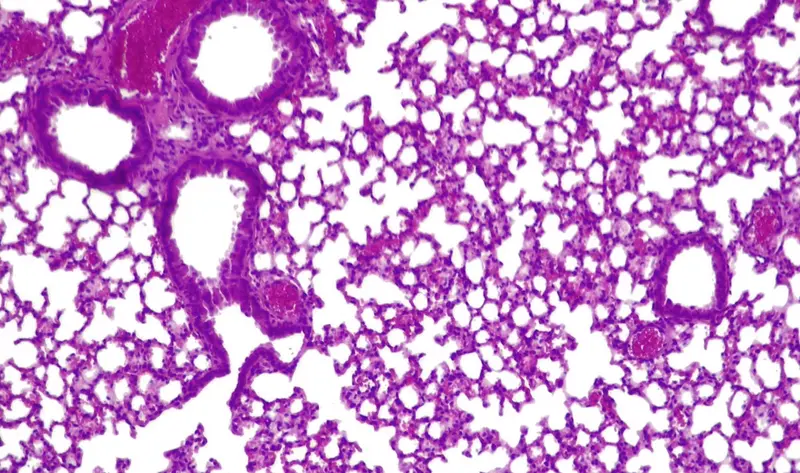

Pulmones de ratón con 'pildora viva' activa combatiendo 'presudomonas aerugionosa' - CGR/PULMOBIOTICS